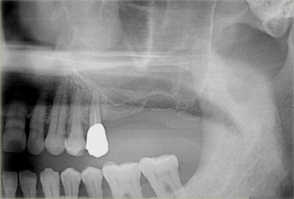

ボーングラフトインプラント(ブロック骨移植をし骨造成をしたインプラント)

ボーングラフトは、十分な量の骨が得られない場合に、骨をブロックで切り出し、移植することで必要な骨を作り出します。

- 主訴

- 上顎前歯の噛む時の痛み

- 治療内容

- 上顎前歯部を抜歯すると大きな骨吸収を予測したため、下顎臼後三角部より骨片を採取し、抜歯時にインプラント埋入と同時に骨造成を行なった

- 治療費用

- 800,000円(税別)

- 治療期間

- 5ヶ月